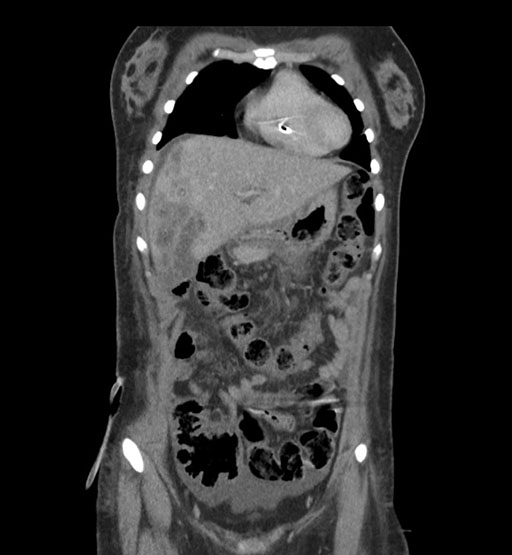

Axial Venous

Coronal Venous